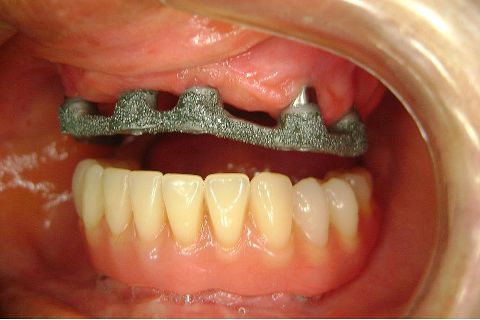

FASE PROTÉTICA DA REABILITAÇÃO EM MAXILA ATRÓFICA...incluindo a reabertura, instalação dos minipilares e PTR provisória reembasada sobre os cilindros de proteção.